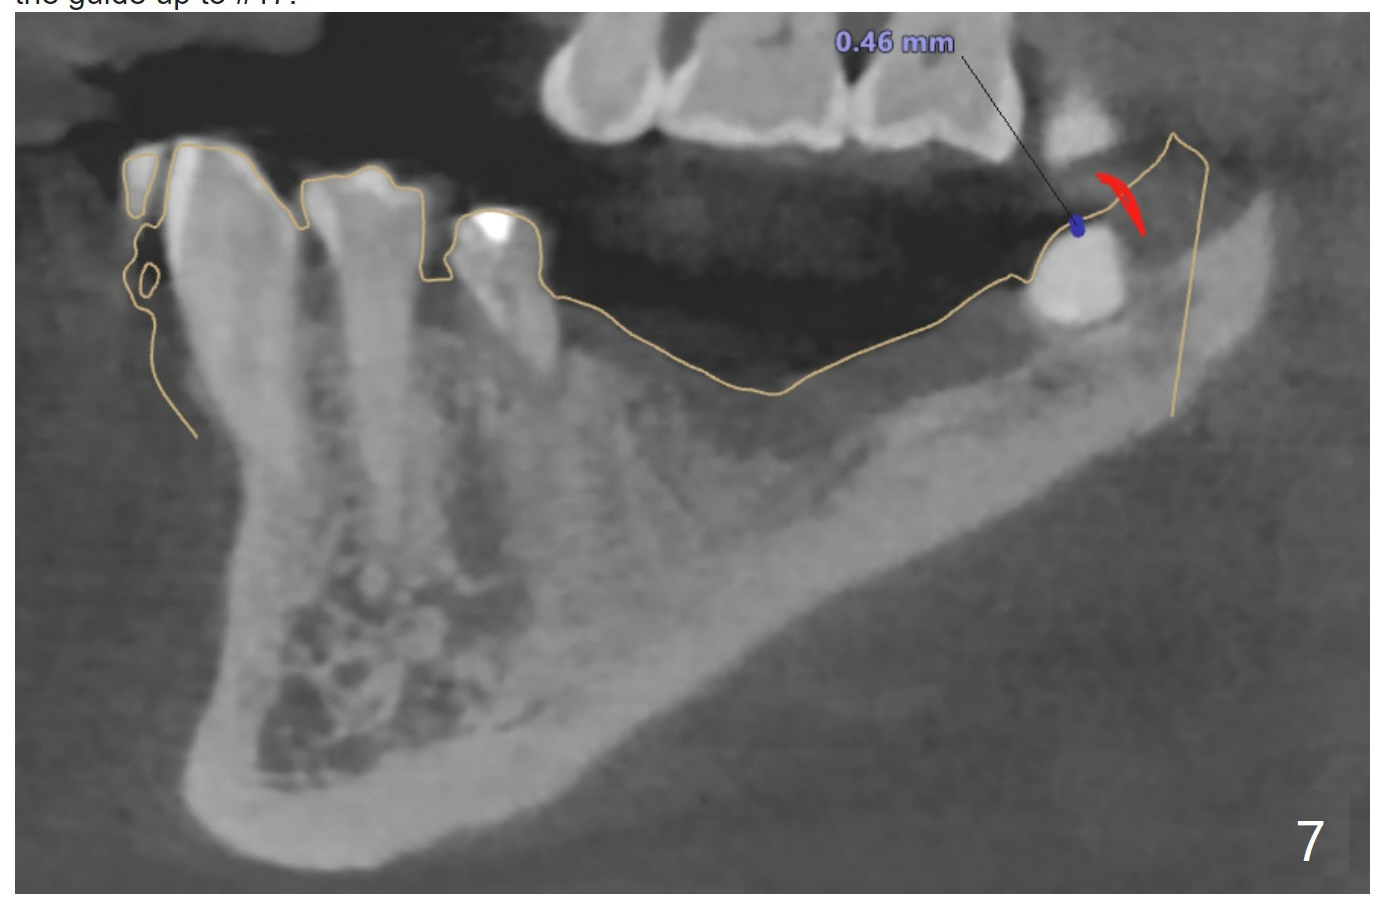

Distal Stop